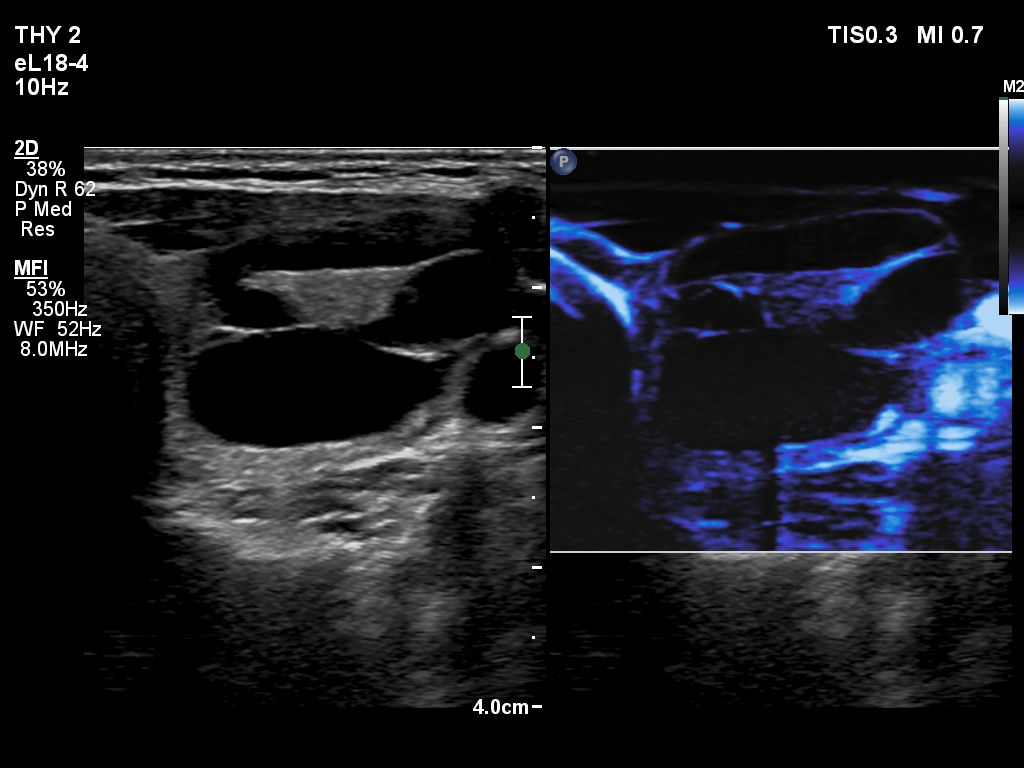

First examination (first and second rows of images):

Clinical presentation: A 25-year-old woman requested evaluation of a neck lump which was discovered by herself 3 weeks ago.

Palpation: an elastic nodule in the left lobe.

Result of blood test: TSH 1.43 mIU/L.

Ultrasonography. The thyroid was echonormal. There was a dominantly cystic nodule in the left lobe. The lesion had echonormal solid area.3.5 mL brown fluid was aspirated. The cyst has begun to refill during the aspiration of the cystic content. Cytology resulted in benign cystic lesion.